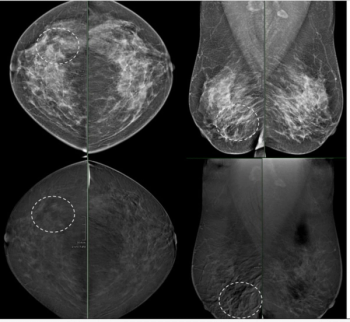

Emerging research suggests that radiomic breast texture features extracted from full-field digital mammography may bolster prognostic assessments of invasive breast cancer risk beyond traditional risk factors.

For DBT breast cancer screening, 47 percent of radiologist-only flagged false positives involved mass presentations whereas 40 percent of AI-only flagged false positive cases involved benign calcifications, according to research presented at the recent American Roentgen Ray Society (ARRS) conference.